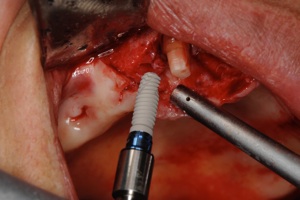

光機能化インプラントの実際の写真

光機能化を行うとインプラントの濡れがよくなり血液が付きやすくなります

血液に触れた瞬間からネジやまに血液が上がってきているのがわかるとおもいます

これによりインプラントの骨に結合する強さ、早さが劇的に改善し、

より患者さんに自信をもってインプラント治療を提供すること可能となりました。